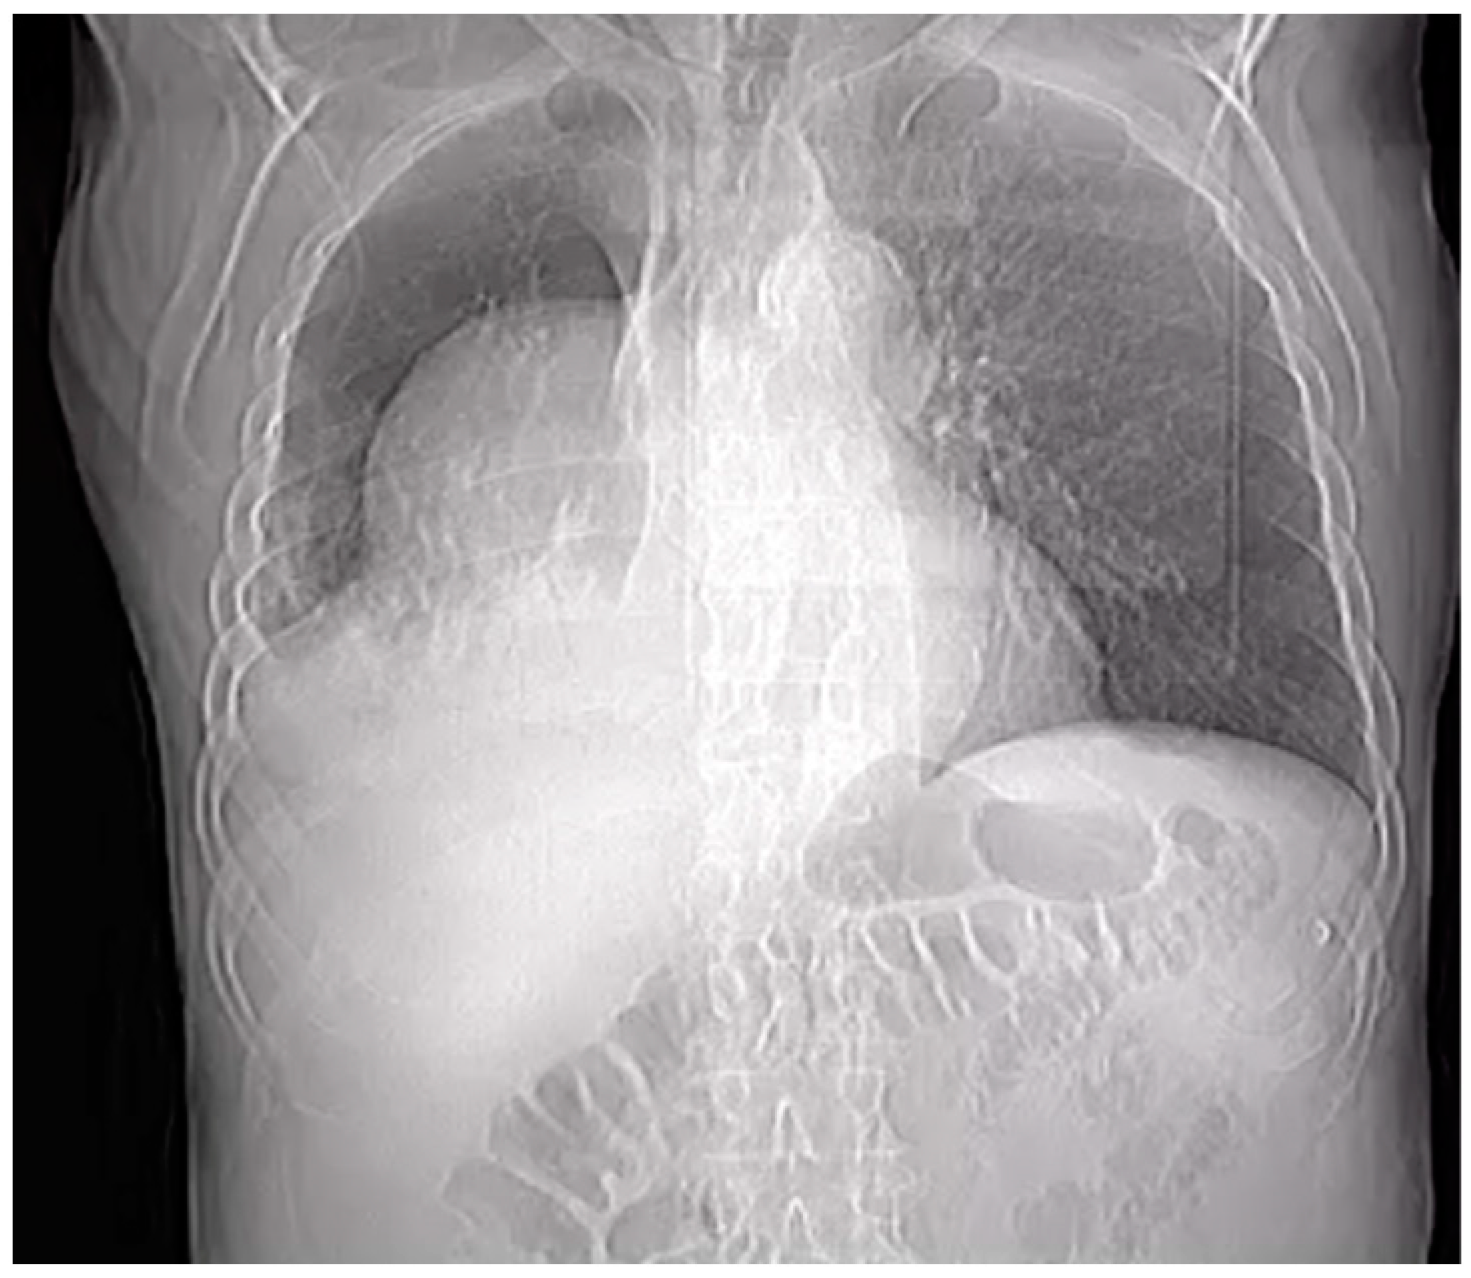

A preliminary chest X-ray was ordered as part of the initial assessment (Figure 1). The radiographic image revealed an abnormality within the right pleural cavity. To elucidate the nature of this radiographic image, a thoracic angiographic computed tomography (CT) scan was deemed essential. The key findings of the imaging study included the below:

Figure 1.

Chest X-ray.